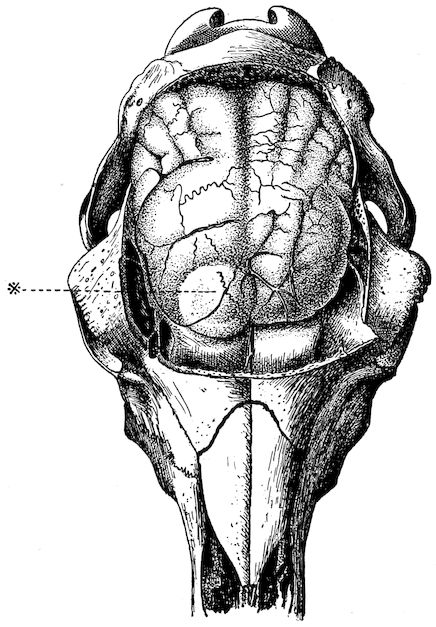

Fig. 1.—Rachitis in a young goat.

Rachitis is a disease of youth, and is common both to the human species and to all domestic animals. It is characterised by irregularities in development and by imperfect consolidation of the bones. The boundary between rachitis and osseous cachexia is difficult to define and in fact at the present moment the two diseases can scarcely be defined with exactitude. Rachitis again is often complicated with softening of the bones, disease of the limbs, arrested development, etc., but it must not be forgotten that although the irregularities in ossification and development of the skeleton are the symptoms most striking to the eye, they do not stand alone, and that from the point of view of development all the tissues, including the muscles, are more or less affected and that most of the physiological functions such as digestion and the secretion of urine are deranged.

Symptoms. The onset is absolutely insidious and the diagnosis of rachitis is never made until nutrition has long been abnormal.

This disturbance of nutrition is revealed by irregularity and abnormality in appetite, by difficulty in rising and moving about, and by the animals lying down for long periods. The subjects are feeble, sluggish and badly developed.

Next supervenes the second phase characterised by deformity of bones. This is of two kinds—deformity in the neighbourhood of joints (deformity or enlargement of the epiphyses) and deformity of the diaphyses. The former results from irregularity in ossification of the articular cartilages. The latter is followed by loss of rigidity in the bones of the limbs which, under the influence of the body weight and of muscular contraction, bend in different directions.

The bones appear of increased thickness principally towards the 6articulations. The latter are deformed, and on palpation are found to be surrounded by uneven and irregular growths.

The front limbs are distorted. In young pigs, lambs, and less frequently in foals, calves and dogs, the jaws become deformed, and mastication is rendered difficult.

The vertebral column may also be affected, and lordosis (bending downwards of the back) or skoliosis (lateral bending of the back) is somewhat frequent.

Cyphosis, or upward bending of the back, seldom occurs, and when seen, sometimes results from disease other than rachitis.

General development is always interfered with and the young creatures are generally dwarfed.

The digestive apparatus is disordered, the appetite is irregular and sometimes depraved, while indigestion, gastritis, and enteritis are not exceptional. Physiological and pathological research has shown that the quantity of phosphoric acid eliminated in twenty-four hours in a rachitic child is double the quantity passed by a healthy infant. The amount of urea in the urine (which is a criterion of nutrition, and usually varies in proportion to the amount of food ingested) is, on the contrary, diminished even when highly nitrogenous food is given, thus suggesting diminution in nutrition.

Lesions. The lesions are represented by abnormal and irregular thickening around the interarticular cartilages. The cartilage is thickened, compressible, very spongy and without regular ossification. Diffused periostitis exists principally towards the extremities of the bone. Beneath the periosteum the surface of the bone appears rough and softened. On section the medullary canals are seen to be enlarged and filled with marrow of a gelatinous character. The Haversian canals are dilated, and the entire tissue appears very vascular. Chemical analysis proves that the mineral constituents of the bone, particularly the phosphates, have diminished by one-half; the organic constituents on the other hand are increased in a similar ratio, but the ossein is abnormal. Ossification has, in a word, been incomplete.